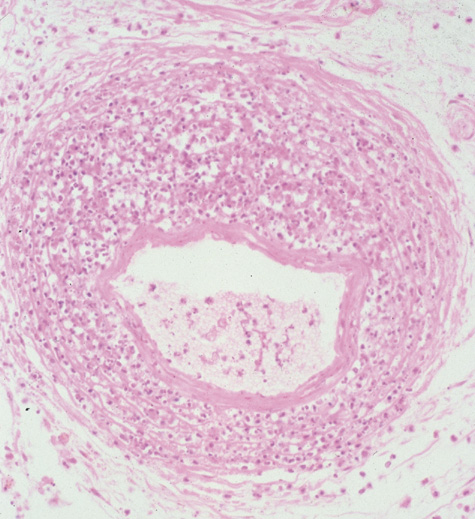

Fig. 24. Mucormycosis. A. A 72-year-old patient with acute myelogenous leukemia and invasive fungal sinusitis presented with orbital cellulitis. B. Involvement of hard palate with eschar. C. Fungi in the posterior ciliary artery.

Diagnosis is made by having a large index of suspicion and obtaining specimens of nasal turbinate, sinus, or infected orbital tissue. Large, branching nonseptate hyphae are readily apparent on hematoxylin and eosin staining or with methenamine silver staining (see Fig. 23). These hyphae can be grown on fungal culture.